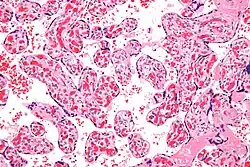

| Micrograph of a chorangiosis. H&E stain. | |

Chorangiosis is a placental pathology characterized by an abundance of blood vessels within the chorionic villi.

It is diagnosed by a microscopic examination of the placenta.

Commonly used criteria from Altshuler[2][3] are: "a minimum of 10 villi, each with 10 or more vascular channels, in 10 or more areas of 3 or more random, non-infarcted placental areas when using a ×10 ocular." The Altshuler criteria are not theoretically rigorous, as they do not define the area. Normal villi have up to five vascular channels.[3]